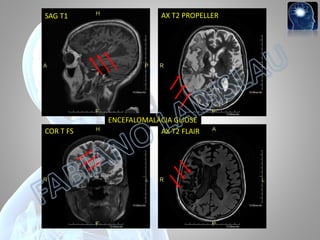

SAG T1 COR TFS AX T2 PROPELLER ENCEFALOMALÁCIA GLIOSE AX T2 FLAIR

Paciente, F, 38a,seqüela de AVCH em idade jovem, etiologia hipertensiva. Encefalomalácia e sangramento antigo.

Paciente, F, 38a,seqüela de AVCH em idade jovem, etiologia hipertensiva.